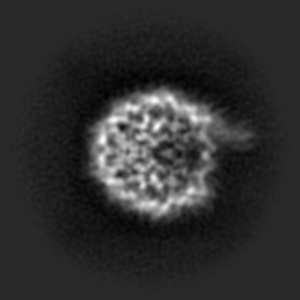

5.4 Denoising real data

In this section we test our method on real data from single-particle Cryo-Electron Microscopy (see Cheng et al., (2015) for an introduction), where many particles of the same type are suspended in liquid, frozen, and put under an electron microscope. This produces extremely noisy D-images which need to be refined before further steps like D reconstruction can be attempted. This presents an opportunity to investigate the performance of our method on practically relevant real world data with non-Gaussian noise. We use the EMPIAR- (Bacic et al.,, 2021) dataset of grayscale images with resolution. They were extracted from raw data and undergone some preprocessing, but are still very noisy (see Figure 8, top left). We trained a DDPM++ model555In order to compensate for the higher resolution we reduced the number of feature channels in the ddpmpp architecture from to , but otherwise used the same settings as for the synthetic data. Training took roughly hours on a two GPUs. on this data and used our method to generate samples (see Figure 8, right) whose shapes correspond strongly to what has been obtained by Bacic et al., (2021), see Figure 8, bottom. We emphasize that the network has only ever seen noisy data and has in no way been specifically adjusted based on a priori knowledge of these shapes. This can be seen by the fact that standard score inference generates noisy samples, very similar to those in the training set (see Figure 13 in the Appendix). The parameters used for Figure 8 of the extended score inference have been determined by hand with such knowledge, of course, but similar results are generated for a wide range of parameter choices (see Figure 12 in the Appendix). In particular, this demonstrates a significant capability of the extended score to guide generation towards samples from the underlying image manifold, also in the case of real data with extreme noise corruption caused by physical measurement modalities. This example serves as proof of concept for the validation of our approach: reaching state-of-the-art performance is outside the scope of this work, and would require incorporating more prior domain knowledge.